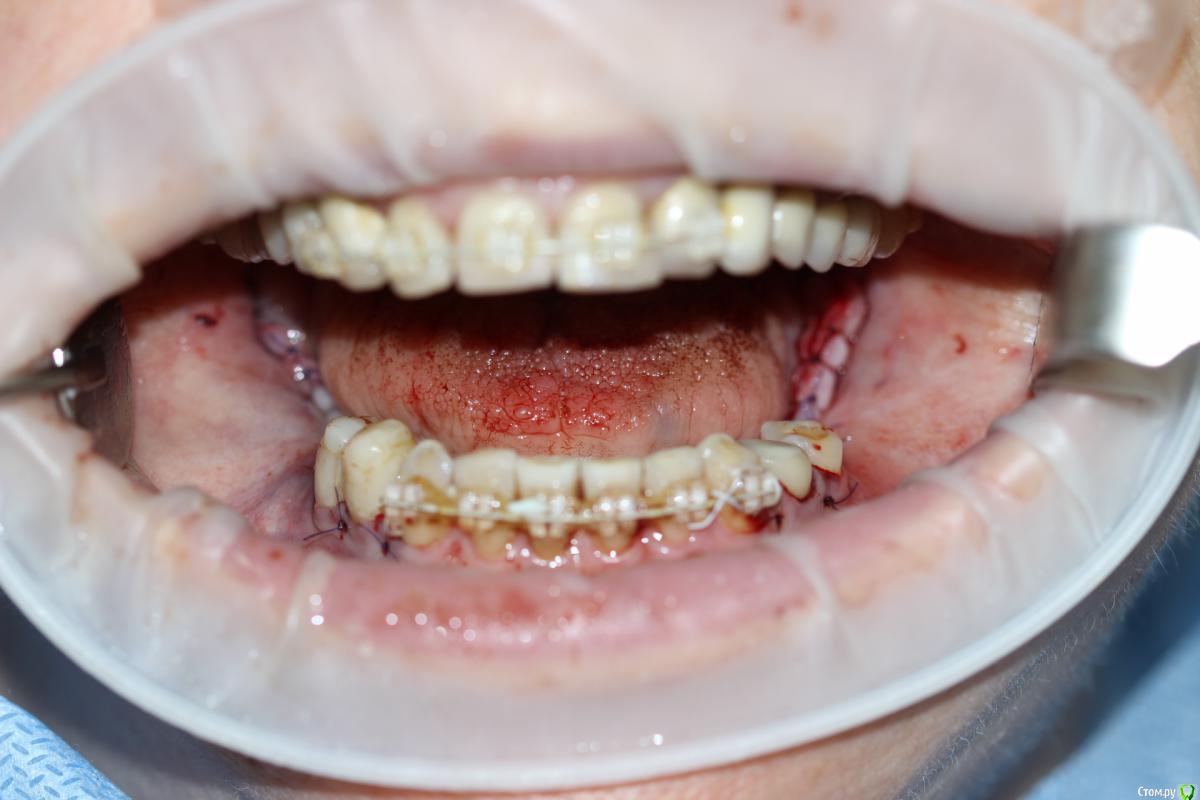

Популярный пост Dantist55 Опубликовано 22 декабря, 2014 Автор Популярный пост Поделиться Опубликовано 22 декабря, 2014 Через 5 месяцев... 21 Ссылка на комментарий

Dantist55 Опубликовано 22 декабря, 2014 Автор Поделиться Опубликовано 22 декабря, 2014 в целом хорошо. но нет деталей где я смогу понять что качественно отработали: 1) кт срезы до и после с замерами чтоб было понятно на сколько нарастили 2)кт срезы с установленными имплантами чтоб было понятно какие болты удалось установить и стало чтоб всем понятно для чего наращивали - ведь вы растили в высоту и в ширину. 3) фото на этапе установленных имплантов - соотношение платформы импланта и уровня кости - заглубили или нет - если да то насколько. Ориентировались ли на будущий зенит зуба. мне понравилось. но чуйка что есть гиперлечение - думаю можно было болты и костную пластику совместить. Растить по высоте я скорее всего бы не стал.КТ посмотрю позже на работе - я в отпуске.По высоте добавляли чтобы зубы не получились большими.Импланты не заглублял, т.к. у XIVE полированная фаска.Насчет гиперлечения может Вы и правы. Эту работу я сделал сразу после приезда от Кури. 2 Ссылка на комментарий